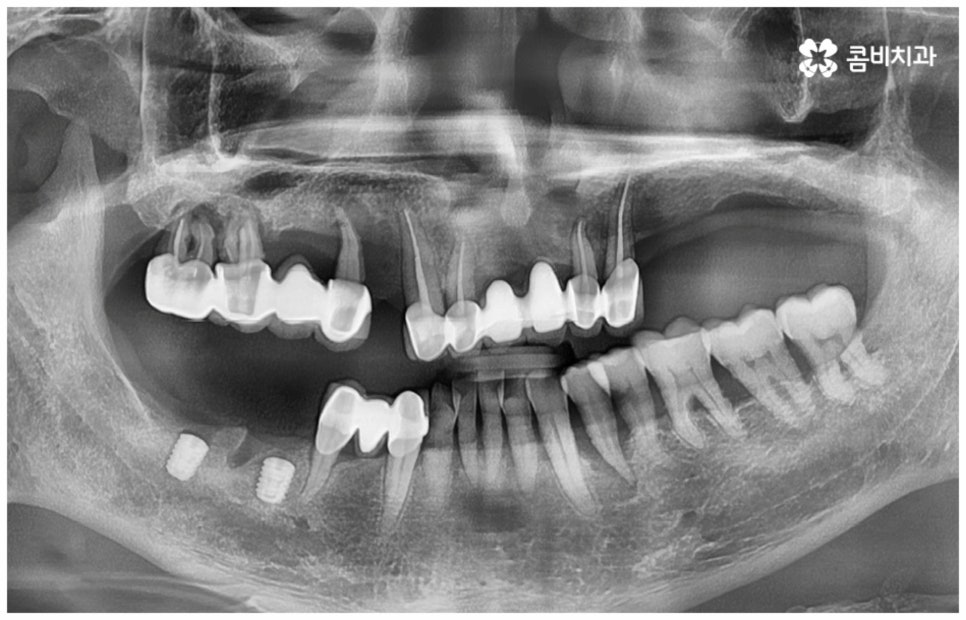

보통 정확한 위치에 식립하고 철저하게 사후 관리를 해 준다면 임플란트수명 은 거의 반영구적이라고 할 정도로 오랫동안 건강하게 사용할 수 있습니다. 그러기 위해서는 처음 식립할 때 환자분들의 상황에 맞게 체계적인 계획을 세워 정밀한 식립을 진행할 수 있는 시술자의 높은 숙련도 외에도 꼼꼼한 검사를 위한 3D-CT 와 같은 정밀 진단 장비를 갖추고 있는지 여부를 살펴보실 필요가 있어요. 이를 통해 환자분들 각각의 구강 구조, 치조골 상태 (밀도나 두께 등), 신경이나 혈관과 같은 주변 조직 등을 정확하게 분석한 다음 오랜 임상데이터를 바탕으로 높은 성공률을 보이고 있는 정품 재료를 사용하여 식립을 진행하는 것이 임플란트수명 을 늘리는데 도움을 주므로 이런 점들 역시 신경써서 살펴보시길 권유드리고 있습니다.